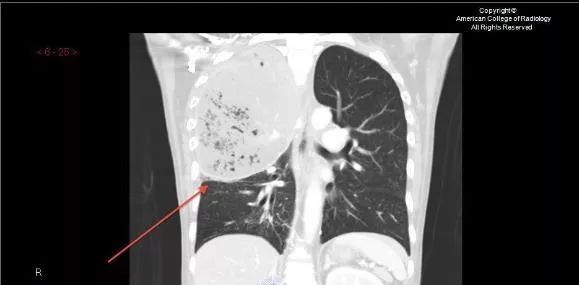

CT:双肺多发空洞、气囊、结节,病灶以胸膜下为主,见实变,胸腔积液。肝脓肿。

CT也提示脓毒肺栓塞!

这个患者的特点是肺空洞,肝脓肿!肝脓肿的存在,大大缩小了诊断范围,缩小了细菌范围!肺CT提示脓毒肺栓塞,并且同时存在肝脓肿,绝大多数都是肺炎克雷伯杆菌,不是金葡菌,真菌更是少见!